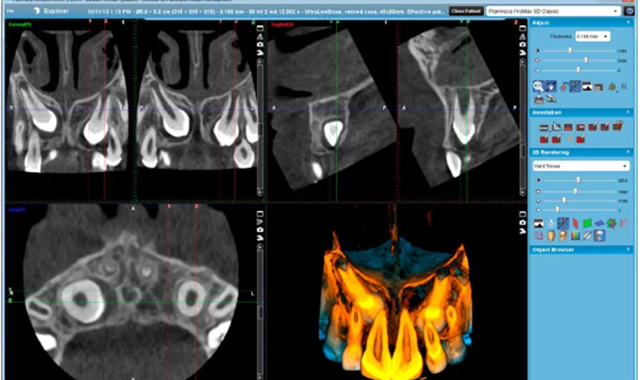

For Dr. Zach Evans, there is no substitute for the integrated capabilities of Planmeca Romexis imaging software. Planmeca Romexis is a modular software program reportedly offering an “all-in-one workflow” for comprehensive digital dentistry. Romexis is designed to manage 2D and 3D imaging including Smile Design and other features for advanced diagnostics. It also manages the restorative design and milling for a complete CAD/CAM solution under one platform.

“We use Romexis all the way from restorative CAD/CAM dentistry to guided implant surgery. The beautiful thing is that [Planmeca] has created software that ties everything together,” he says, describing Romexis as a single-software interface that integrates a variety of workflows.

For Dr. Evans, the benefits of integrated workflow go beyond mere efficiency. “It has the benefit of higher-quality clinical outcomes because we are not skipping steps,” he says. “For example, if I’m planning an implant case, I’m using the CAD/CAM module... I can take advantage of the power of that application and create a high-quality digital restorative design of the surgical case. That information is immediately available in the 3D imaging and implant planning module, allowing me to do virtual implant planning and implant guide design that’s completely restoratively driven.”

According to Dr. Evans, the critical element is having a high-quality diagnostic digital wax-up of the surgical case. That wax-up must consider esthetics, function, and occlusion. Most other systems do not allow a full digital wax-up, he says. Romexis allows you to do it easily within one software system.

“The magic happens when things get complicated,” says Dr. Evans, specifically referring to anterior esthetic implant and restorative cases. For these, his team uses the Romexis Smile Design module. The Smile Design module allows the dentist to create a 2D model of the patient’s future smile, which drives case acceptance.

“More importantly, it gives the dentist a reference point for generating the diagnostic and restorative wax-ups needed to plan a difficult anterior esthetic case,” he says. Bringing the 2D Smile Design model into the CAD/CAM module for the 3D wax-up allows the dentist to determine how the shape, size, and position of the teeth will relate to the true facial esthetics, he explained.